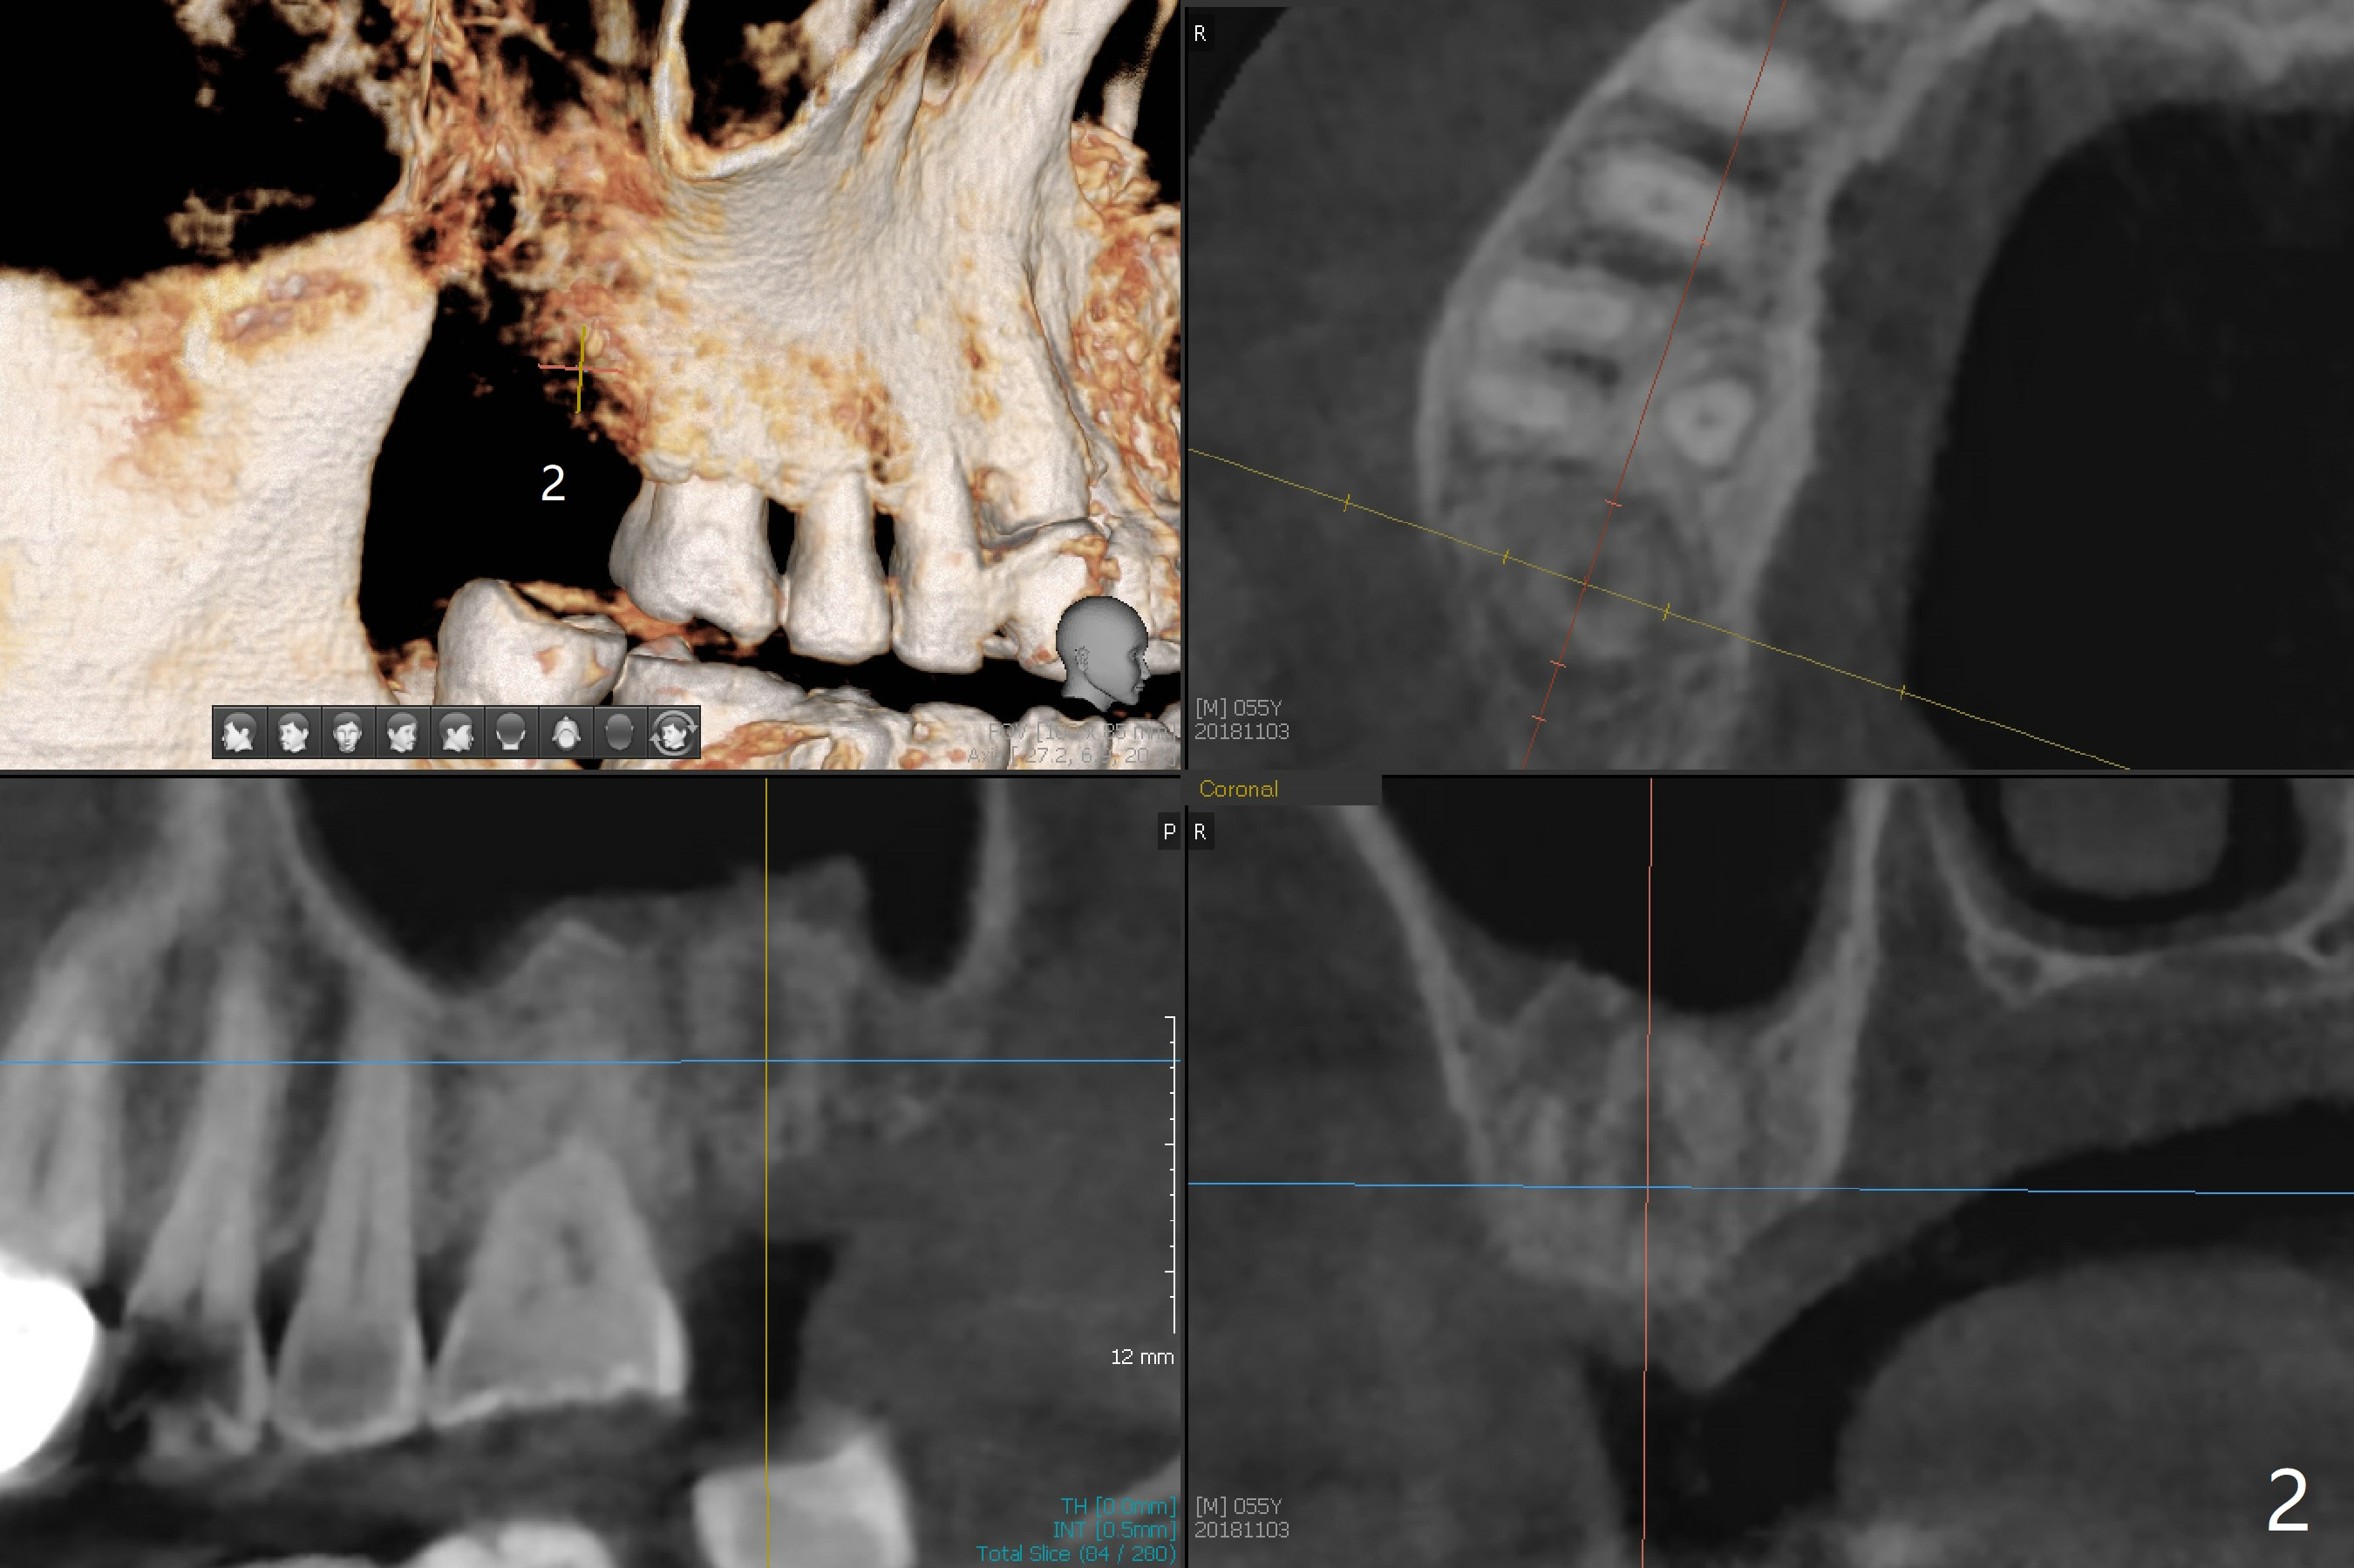

A 55-year-old man with chronic sinusitis, gagging and bruxism returns for #2 implant redo nearly 4 months post implant removal and bone graft (Fig.1). It appears that the site heals with ~ 860 HU (Fig.2). Considering history of chronic sinusitis, a 5x10 mm implant seems too long (Fig.3). For active gag reflex, a 5x11.5 mm implant may be also too long at #19 (Fig.4).